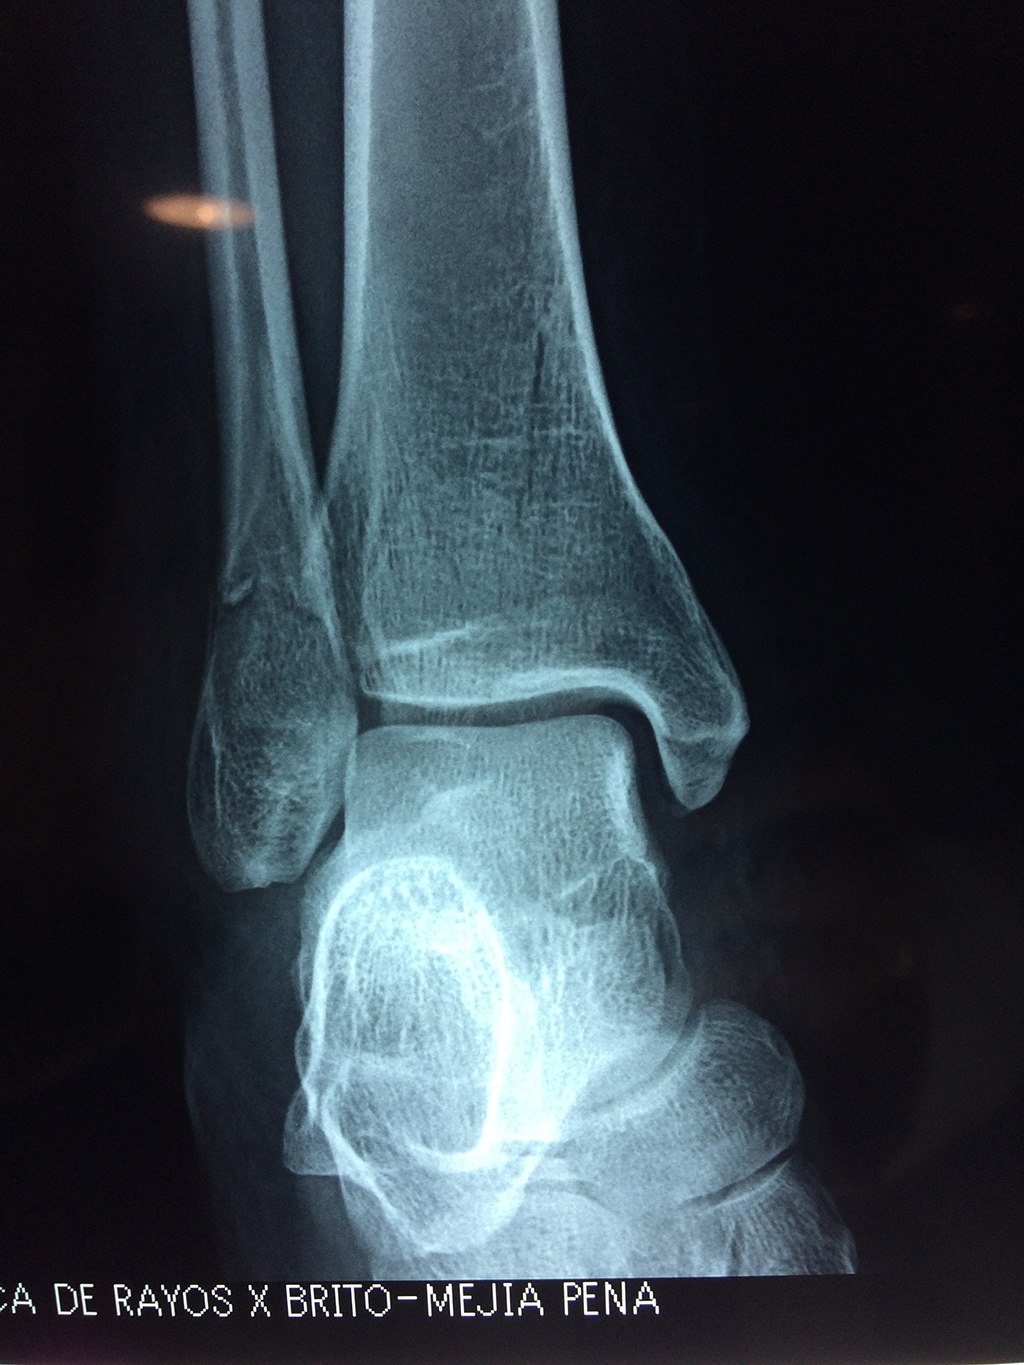

Una fractura de tobillo es la rotura de uno o más de los huesos del tobillo. Estas fracturas pueden ser:

- Producirse en uno o ambos lados del tobillo.

- Los extremos de los huesos están desalineados entre sí (desplazados).

- La fractura se extiende hasta la articulación del tobillo (fractura intra-articular).